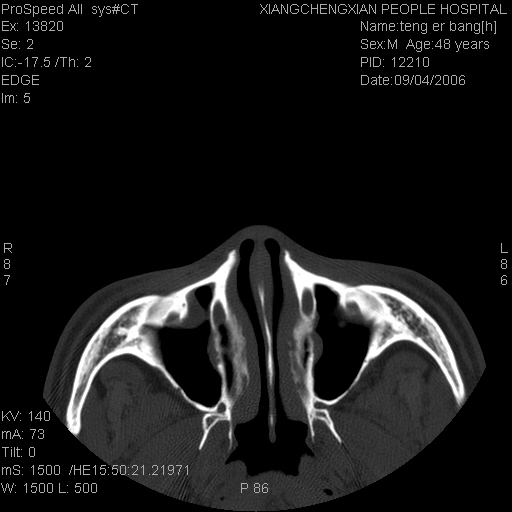

患者,男,以头面部外伤后头疼1小时为主诉入院,患者1小时前被他人打伤头部及左侧面部,眼睑无水肿,左侧面部肿胀压疼,未触及骨擦音。专科检查:耳鼻喉未见异常。

ct:平扫+冠扫:双侧鼻骨对比,冠扫s6#示右侧鼻骨尖部可见线状低密度影,边缘光滑,并见硬化.软组织未见肿胀.

诊断意见:鼻额缝(鼻骨与上颌骨额突缝),但个别同志认为是骨折.因此请同行们会诊.多谢了!

正常鼻颌缝。软组织无肿胀。鼻腔无积液积血。鼻骨光滑规整无中断。均不支持骨折。

正常的,双侧对称.边缘光整,且逢等宽.

正常鼻颌缝。软组织无肿胀。鼻腔无积液积血。鼻骨光滑规整双侧对称。均不支持骨折。